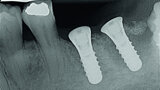

Digitising your implant practice